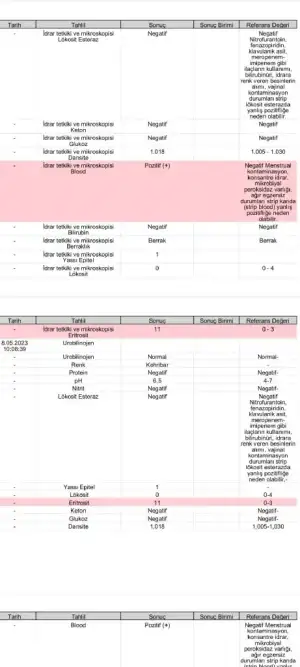

5 Mayıs akşamı yoğun kanamayla kontrole gitmiştim. Bugün tekrar gittim Allah’ıma şükürler olsun bebiş iyi durumu kalp atışı stabil 10+1 im ama 10+4 ölçüldüm. Bebişin boyu da büyümüş

plasenta damarlara yakın yere denk gelmiş buradaki kılcal damarların kanayabileceğini söyledi perinatolugum. Şuan bir kanama alanı yok . Ama koyu siyah gibi kahve gibi hafif peçeteye gelen lekelenmeler devam ediyor ama normalmiş. Lekelenmelerin tamamen geçmesini bekliyoruz rahim ağzı yetmezliğim olduğu için dikiş planlanacak o zamana kadar ve bundan sonra inşallah hiç kanamaz